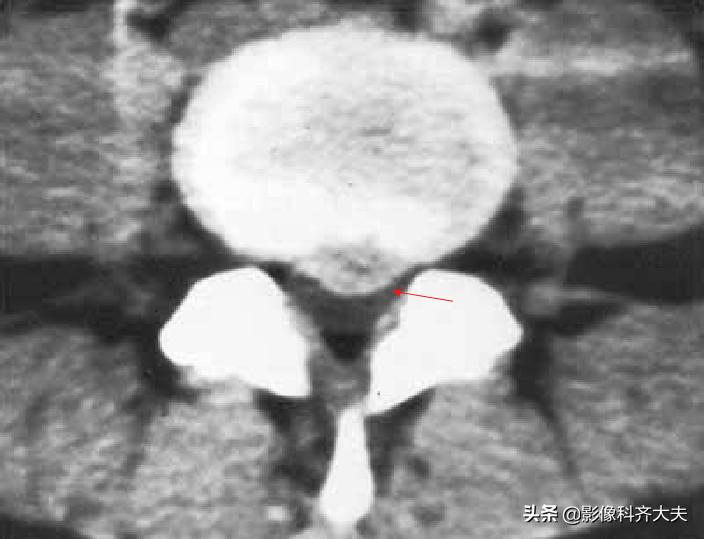

CT:椎间盘突出(中央型)